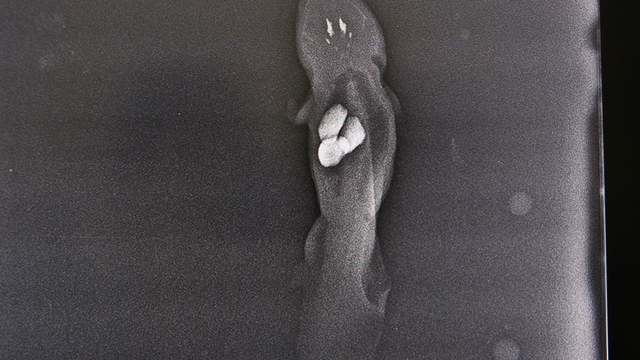

KAYSERİ’de akvaryumdaki taşları yutan aksolotl balığı, anestezi işlemi uygulanıp, ameliyat edildi. Veteriner hekim Esma Erer, operasyona ilişkin, "Akvaryumda süs balığı olarak yetiştirilen aksolotl balığı, çakıl taşlarını yuttuğundan, sindirim sistemi problemiyle getirildi. Röntgen ve klinik muayenelerde yaklaşık 1 santimetre boyutunda 3 taş tespit edildi. Türkiye’de nadir olduğu için çok fazla bu vakalarla karşılaşmıyoruz. Karşılaştığımız zaman da genellikle operasyonla çözüm bulunuyor” dedi.

Operasyon sürecini anlatan veteriner hekim Esma Erer, “Bu yaptığımız operasyon, Türkiye’de ilk değil. Daha önce aynı vaka ile başka üniversitelerde kliniğe başvurulmuştur. Akvaryumda bir süs balığı olarak yetiştirilen 'Axolotl (aksolotl)' balığı çakıl taşlarını yutması ve sindirim sistemi problemiyle kliniğimize getirildi. Röntgen ve klinik muayeneler neticesinde yaklaşık 1 santimetre boyutunda 3 adet taş tespit edildi. Bunun sonucunda balığın ameliyatla midesindeki yabancı cismin çıkarılmasına karar verilmiştir. Balık anestezi altında su içerisinde karın bölgesinden yaklaşılarak mideye ulaşıldı. Daha sonra mide açıldı ve balığın midesi içerisindeki 3 adet yabancı cisim çıkarıldı. Yabancı cisim çıkarıldıktan sonra hayvan uyandırıldı. Daha sonra da hasta sahibine teslim edildi. Sonrasında ise hasta sahibi düzenli olarak kontrole getirdi. Şu anda ise balığın durumunun gayet iyi olduğunu biliyoruz” diye konuştu.